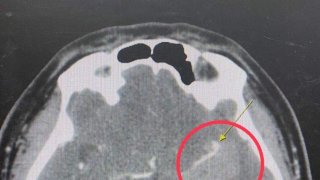

"หมออารักษ์" โพสต์เผยเคสผู้ป่วยวัย 32 ปวดศีรษะเป็นโรคเส้นเลือดสมองโป่งพอง เสี่ยงพิการ เสียชีวิตได้